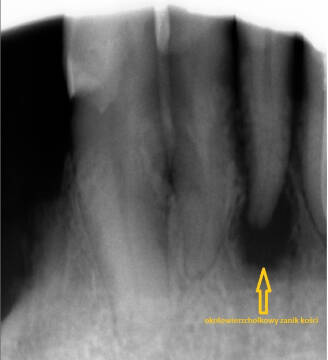

Przekonanie, że ząb wyleczył się sam i dlatego już nie boli, jest błędnym przekonaniem, które może prowadzić do poważnych konsekwencji dla zdrowia. Samoistne ustąpienie bólu w większości przypadków oznacza, że w zębie doszło do obumarcia żywych tkanek. Oznacza to jednocześnie, że proces chorobowy obejmujący ząb trwa w nim nadal, ale utracił on zdolność do "ostrzegania bólem". Powikłania takiego stanu mogą się ujawnić nawet po bardzo długim czasie tworząc ropnie, torbiele czy zmiany okołowierzchołkowe. Procesem chorobowym może być objęta kość żuchwy lub szczęki. Mimo, że już nie boli ząb powinien skonsultować dobry stomatolog, który zkwalifikuje go do dalszego leczenia w zakresie stomatologii zachowawczej, chirurgii szczękowej lub endodoncji. Nie należy zwlekać do czasu, aż powstaną duże zmiany w wyniku zapalenia tkanek lub nieodwracalnie zniszczone zostaną korzenie objęte procesem chorobowym. Prawdopodobnie konieczne będzie wykonanie RTG zębów pod postacią zdjęcia pojedynczego zęba lub panoramicznego RTG zębów uwidaczniającego całość zgyzu wraz z kością żuchwy i szczęki.